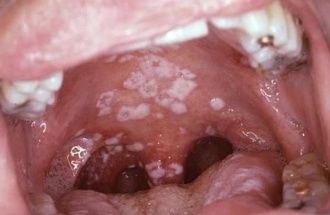

1. Candida bucofaringea

1. placas blanquecinas, adherentes, indoloras aisladas o confluentes

1. lesiones en pacientes jóvenes debe de investigarse infección subsecuente por VIH

1. Tratamiento: Trociscos de Clotrimazol ó Nistatina